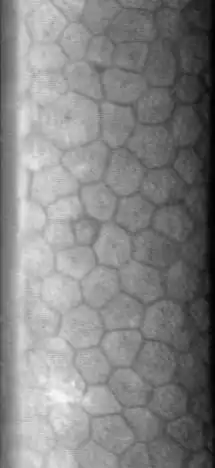

The corneal endothelium is a single layer of endothelial cells on the inner surface of the cornea. It faces the chamber formed between the cornea and the iris.

The normal corneal endothelium is a single layer of uniformly sized cells with a predominantly hexagonal shape. This honeycomb tiling scheme yields the greatest efficiency, in terms of total perimeter, of packing the posterior corneal surface with cells of a given area. The corneal endothelium is attached to the rest of the cornea through Descemet's membrane, which is an acellular layer composed mostly of collagen IV.